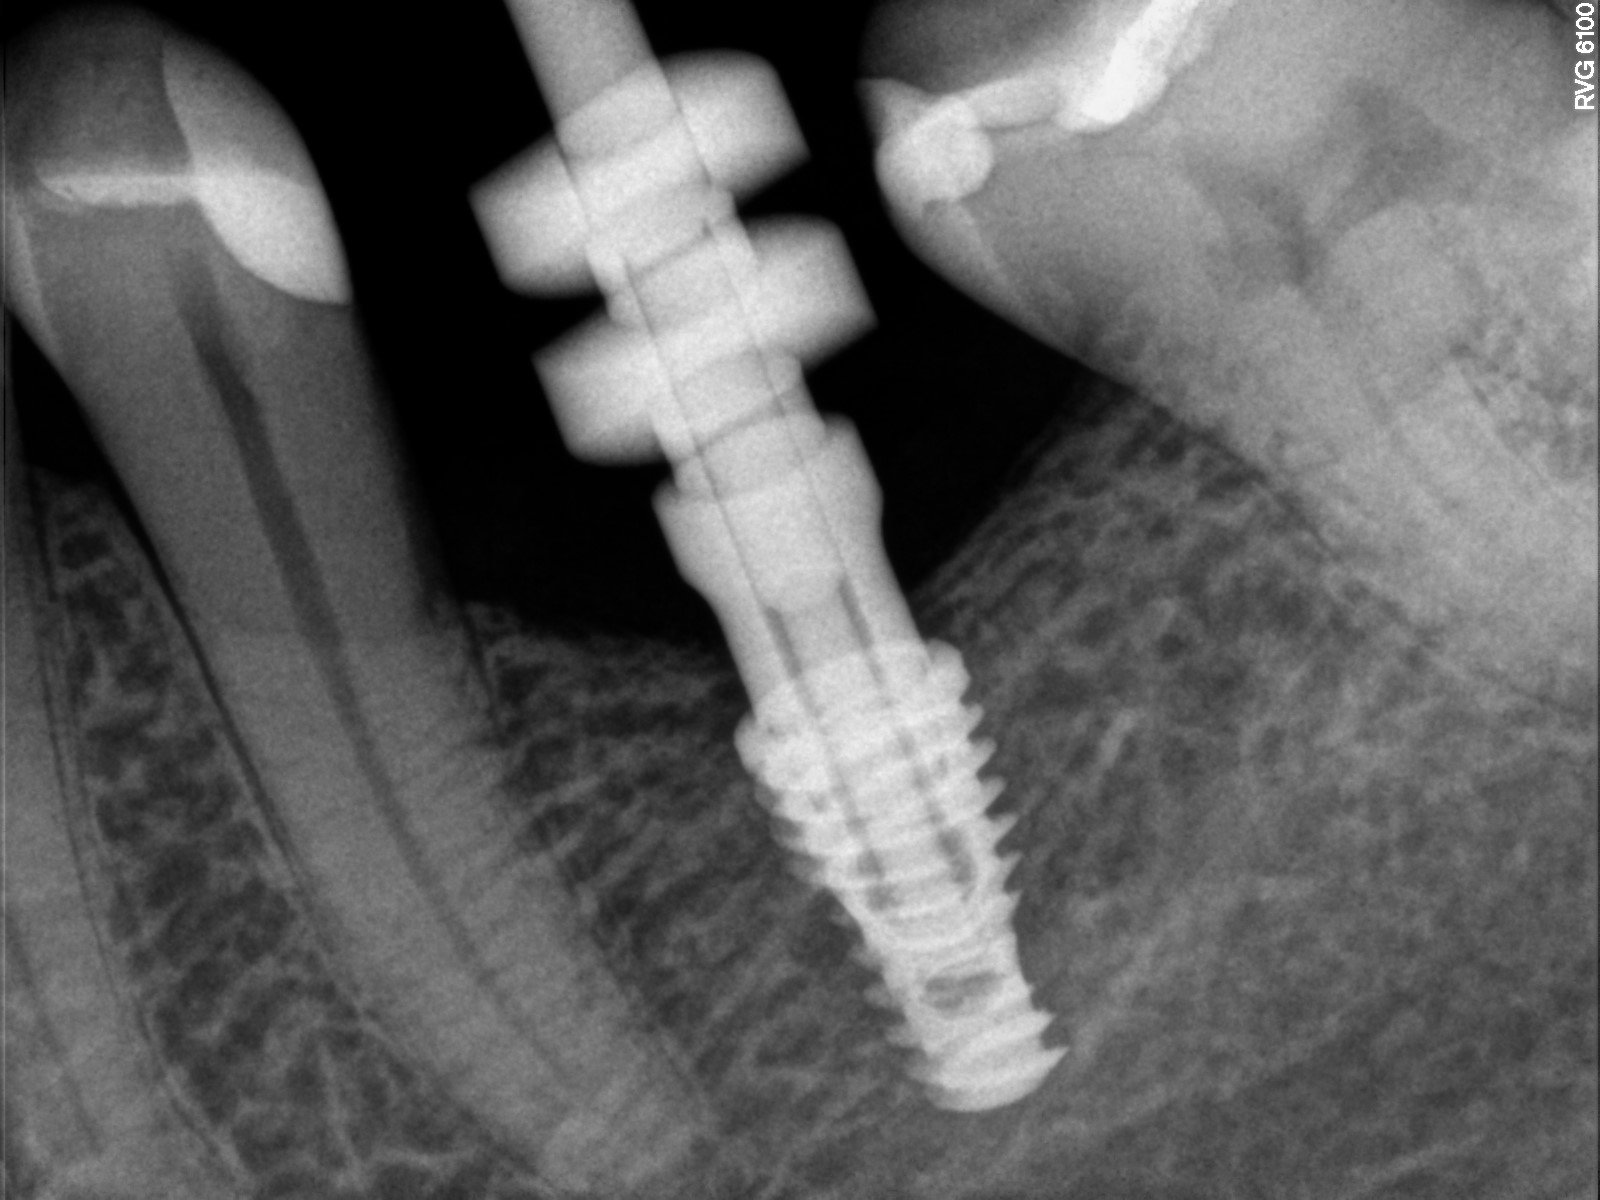

- Implantacja zębów: Przygotowanie jamy ustnej do implantacji często wymaga przeprowadzenia zabiegów chirurgicznych, takich jak augmentacja kości czy podniesienie dna zatoki szczękowej. W naszym gabinecie zapewniamy kompleksową opiekę w tym zakresie.